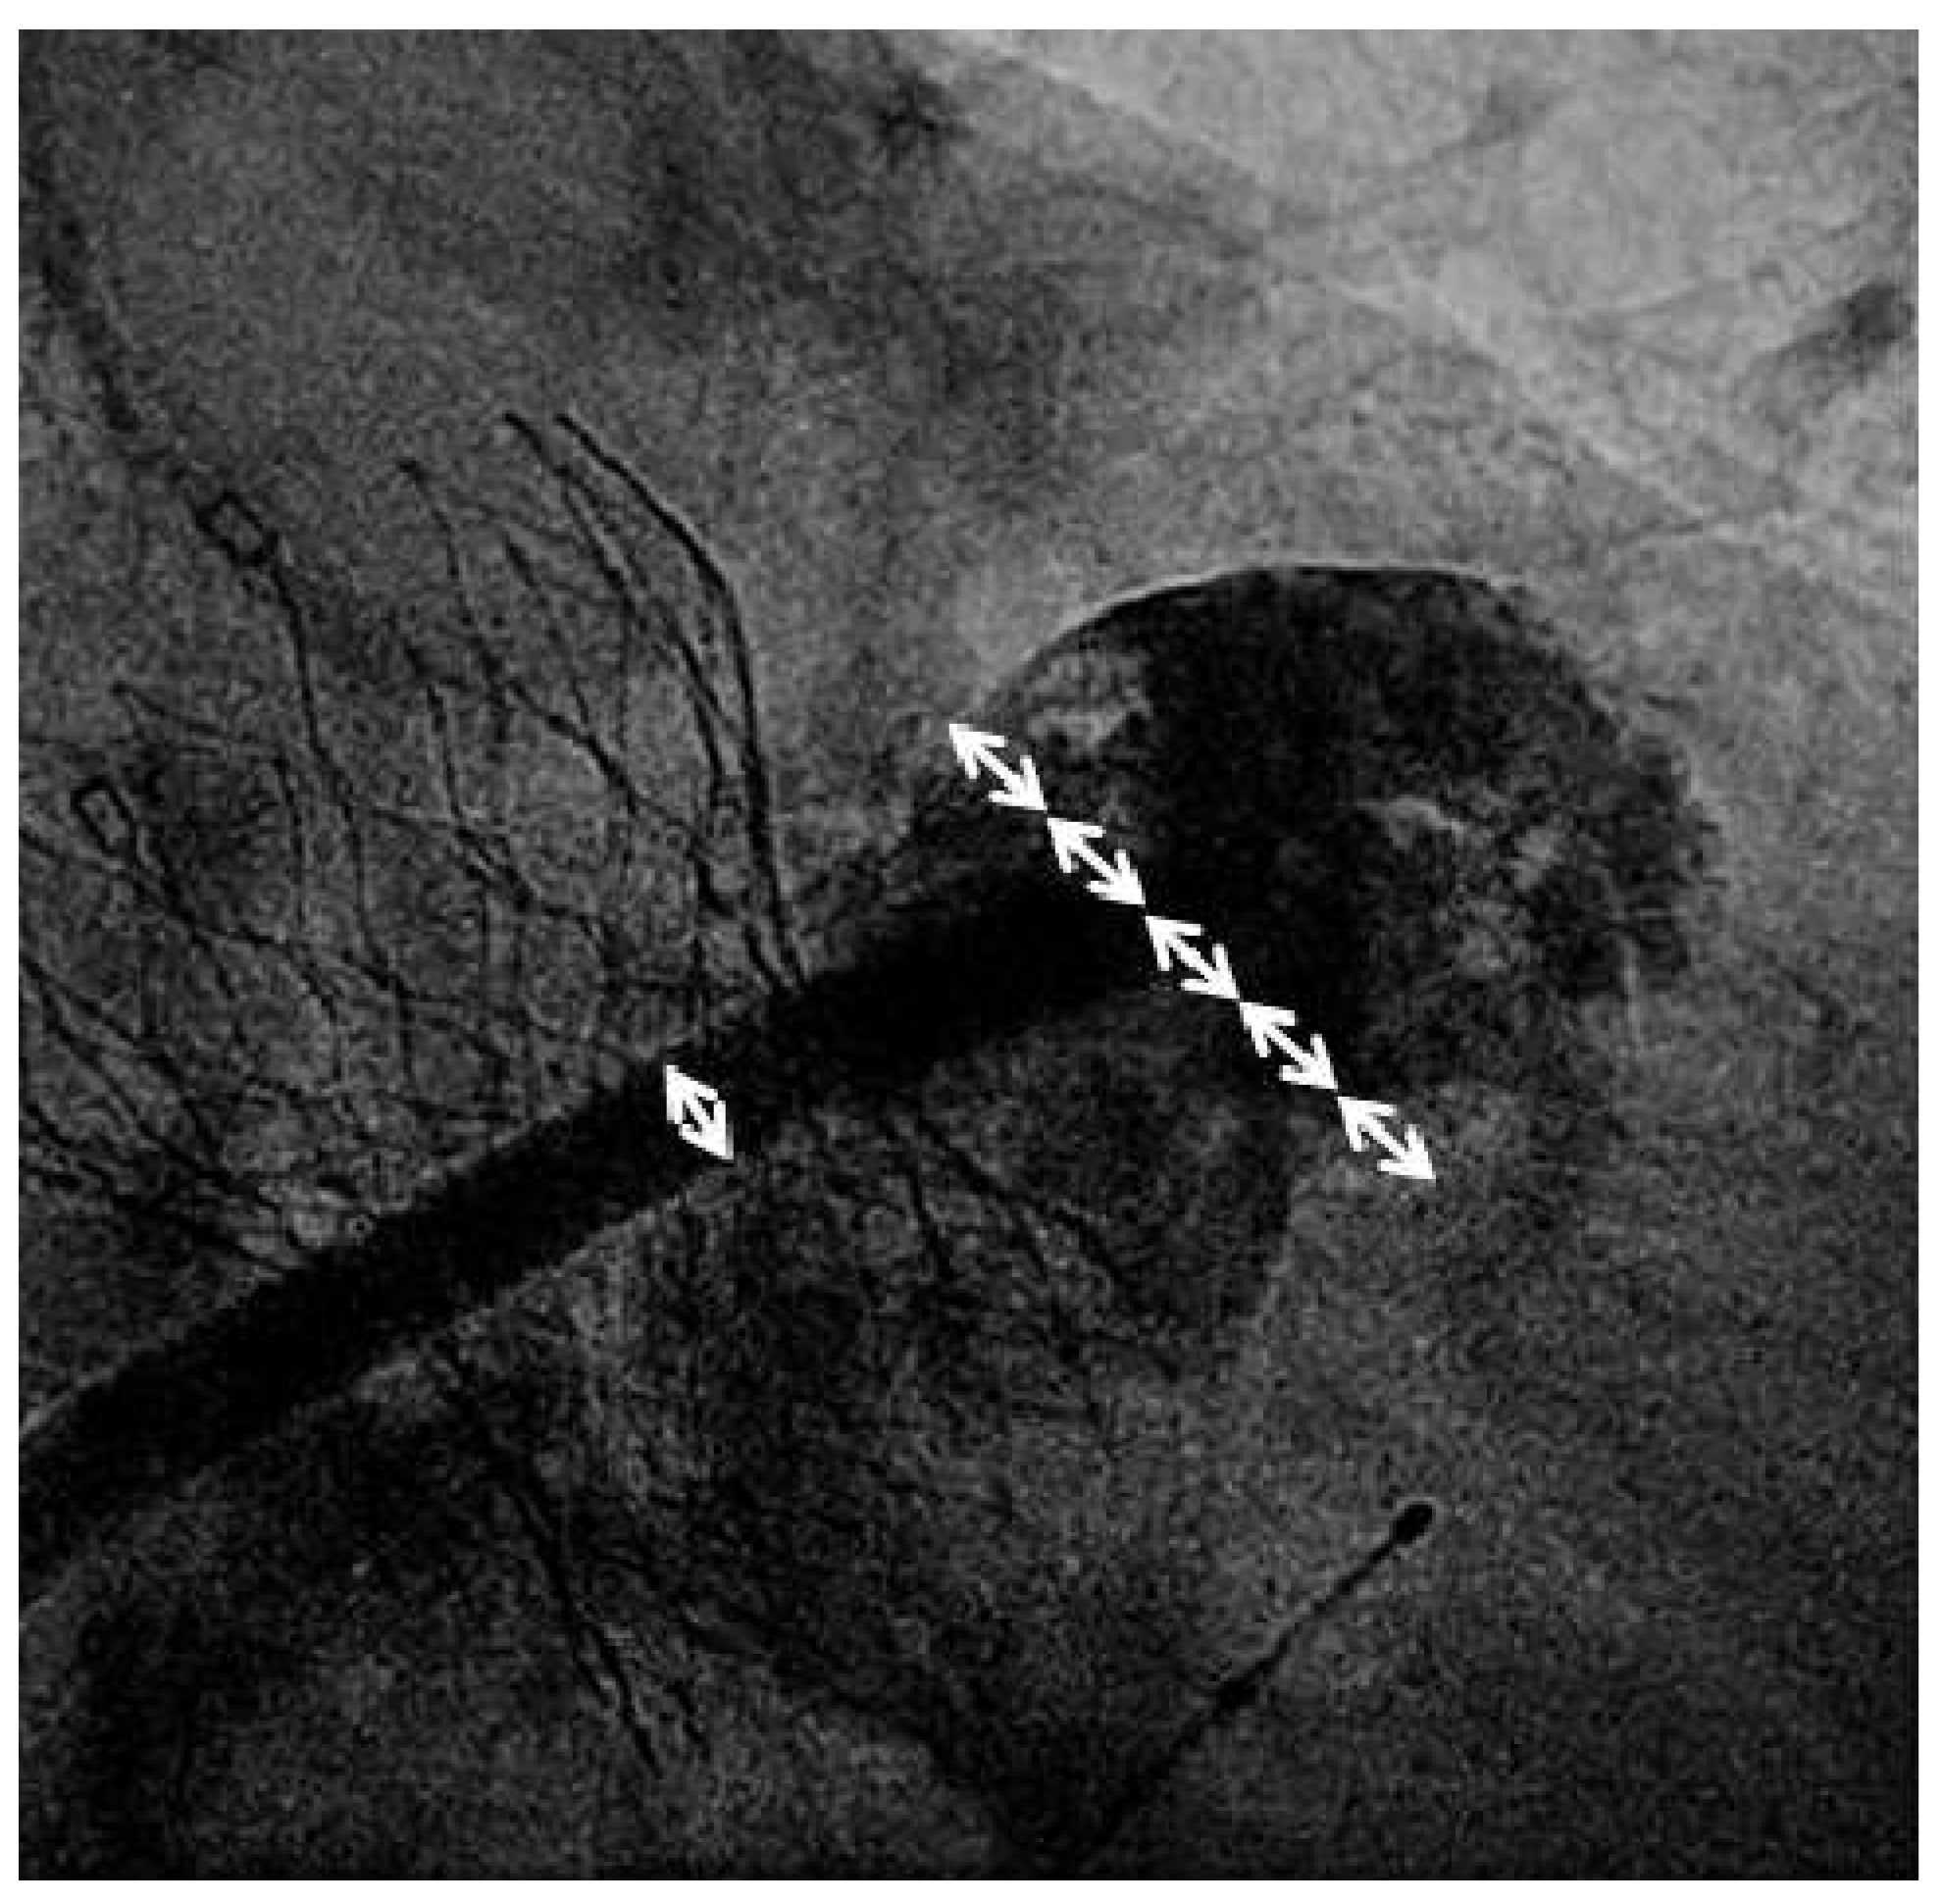

Valve implantation was followed by transseptal puncture through a right femoral venous access using an 8French Mullins transseptal sheath and the Brockenbrough Curved Needle (Medtronic, Minneapolis, USA). Using contrast injections through the transseptal sheath, the left atrial appendage (LAA) was visualised and a thrombus within the left atrial appendage was not detected. The transseptal sheath was replaced by the Amplatzer TorqueVue 45×45 sheath (St. Jude Medical, St. Paul, USA). Sizing of the left atrial appendage was performed using the outer diameter of the delivery sheath as a reference (14F; 5.4 mm; Figure 1). An Amplatzer Amulet 28 mm LAA-Occluder (St. Jude Medical, St. Paul, USA) was deployed in the left atrial appendage in a stable position with good sealing (Figure 2).

Figure 1. Fluoroscopic sizing of the left atrial appendage (LAA) landing zone: the outer diameter of the 14F sheath measures 5.4 mm (single white arrow). The device landing zone measured approx. 23 mm (almost 4.5x the outer diameter of the sheath; serial white arrows). Therefore, a 28 mm device was chosen.